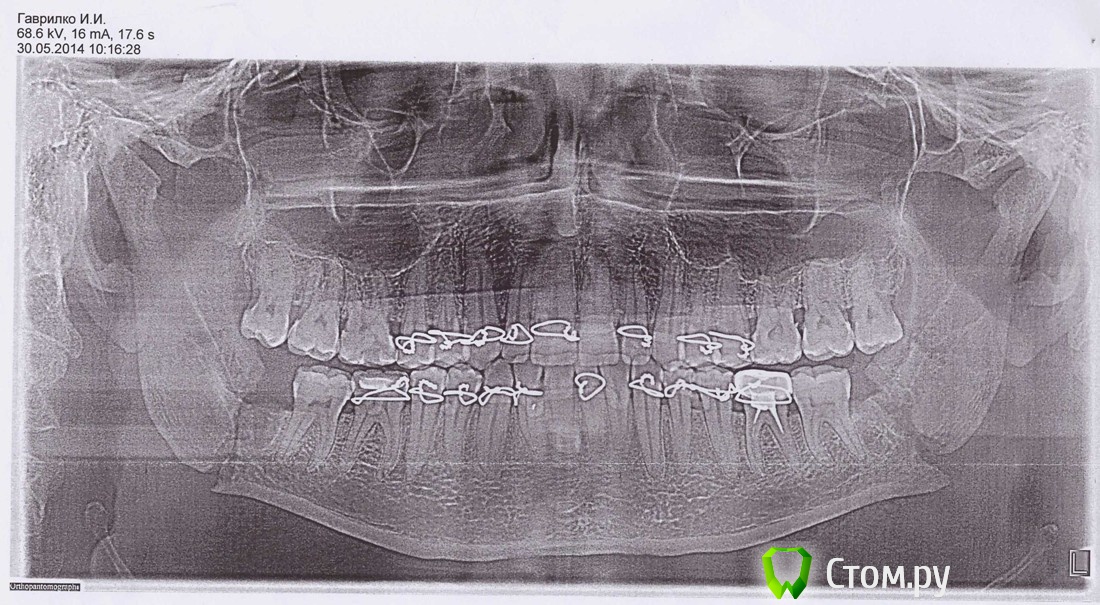

ivanich 82 Опубликовано 30 июня, 2014 Автор Поделиться Опубликовано 30 июня, 2014 Вот посмотрите снимки за 11.06. и за 23.06. Где за 23 немного дернулся при снимке, вот как по середине и съехала челюсть. Скажите, что по снимкам, все правильно сопоставлено и срастается? Ссылка на комментарий

Acidrocker Опубликовано 30 июня, 2014 Поделиться Опубликовано 30 июня, 2014 Вот посмотрите снимки за 11.06. и за 23.06. Где за 23 немного дернулся при снимке, вот как по середине и съехала челюсть. Скажите, что по снимкам, все правильно сопоставлено и срастается?По снимкам все сопоставлено замечательно. То, что посередине - дефект снимка. Ссылка на комментарий

ivanich 82 Опубликовано 1 июля, 2014 Автор Поделиться Опубликовано 1 июля, 2014 Уважаемые форумчане, был сегодня на приеме в ЧЛХ Окружной больницы г. Сургута ХМАО-Югра, сделали еще снимок, сказали операция проведена правильно, но так как стоматолог-хирург снял мне резиновые тяги очень рано и заставил разрабатывать челюсть, произошла небольшая трещина в месте перелома (данное место отмечено стрелочкой), связали впереди челюсть вновь резиновыми тягами и сказали так ходить еще месяц. Но зубы передние не совпадают, получается все равно как буд-то нижняя челюсть выехала вперед, сейчас зубы впереди болят, хотя и не соприкасаются. Беспокоят зубы, которые я отметил красным, сверху они расшатались очень, а снизу почему-то настолько оголились корни, что мне стало страшно. Почти неделю полоскал "Стоматофитом" и пил "Кальцемин". Подскажите, что все таки произошло с зубами или прикусом? Как сохранить зубы, чтобы после дай бог снятия, тяг, не выпали зубы. Начинает нападать деприсняк(((((((((((( Ссылка на комментарий